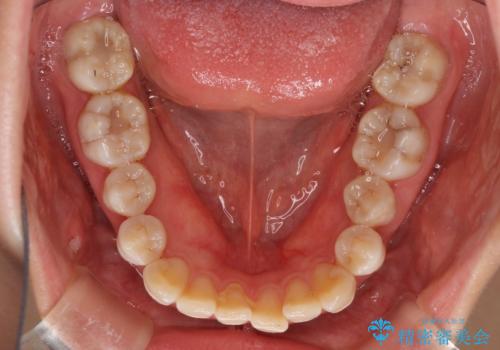

話しにくいオープンバイト インビザラインによる矯正治療

- 前歯の上下スペースによる話しにくさを気にして来院された患者様です。

インビザラインにより上下の前歯の隙間を閉じていくこととしました。

上下の奥歯を圧下させるようにすることで、前歯を接触させるように計画しました。

隙間に舌が入り込むことが話しにくさに繋がっていたため、舌の筋肉のトレーニングも並行して行い、話しにくさの改善と後戻りの抑制を図りました。